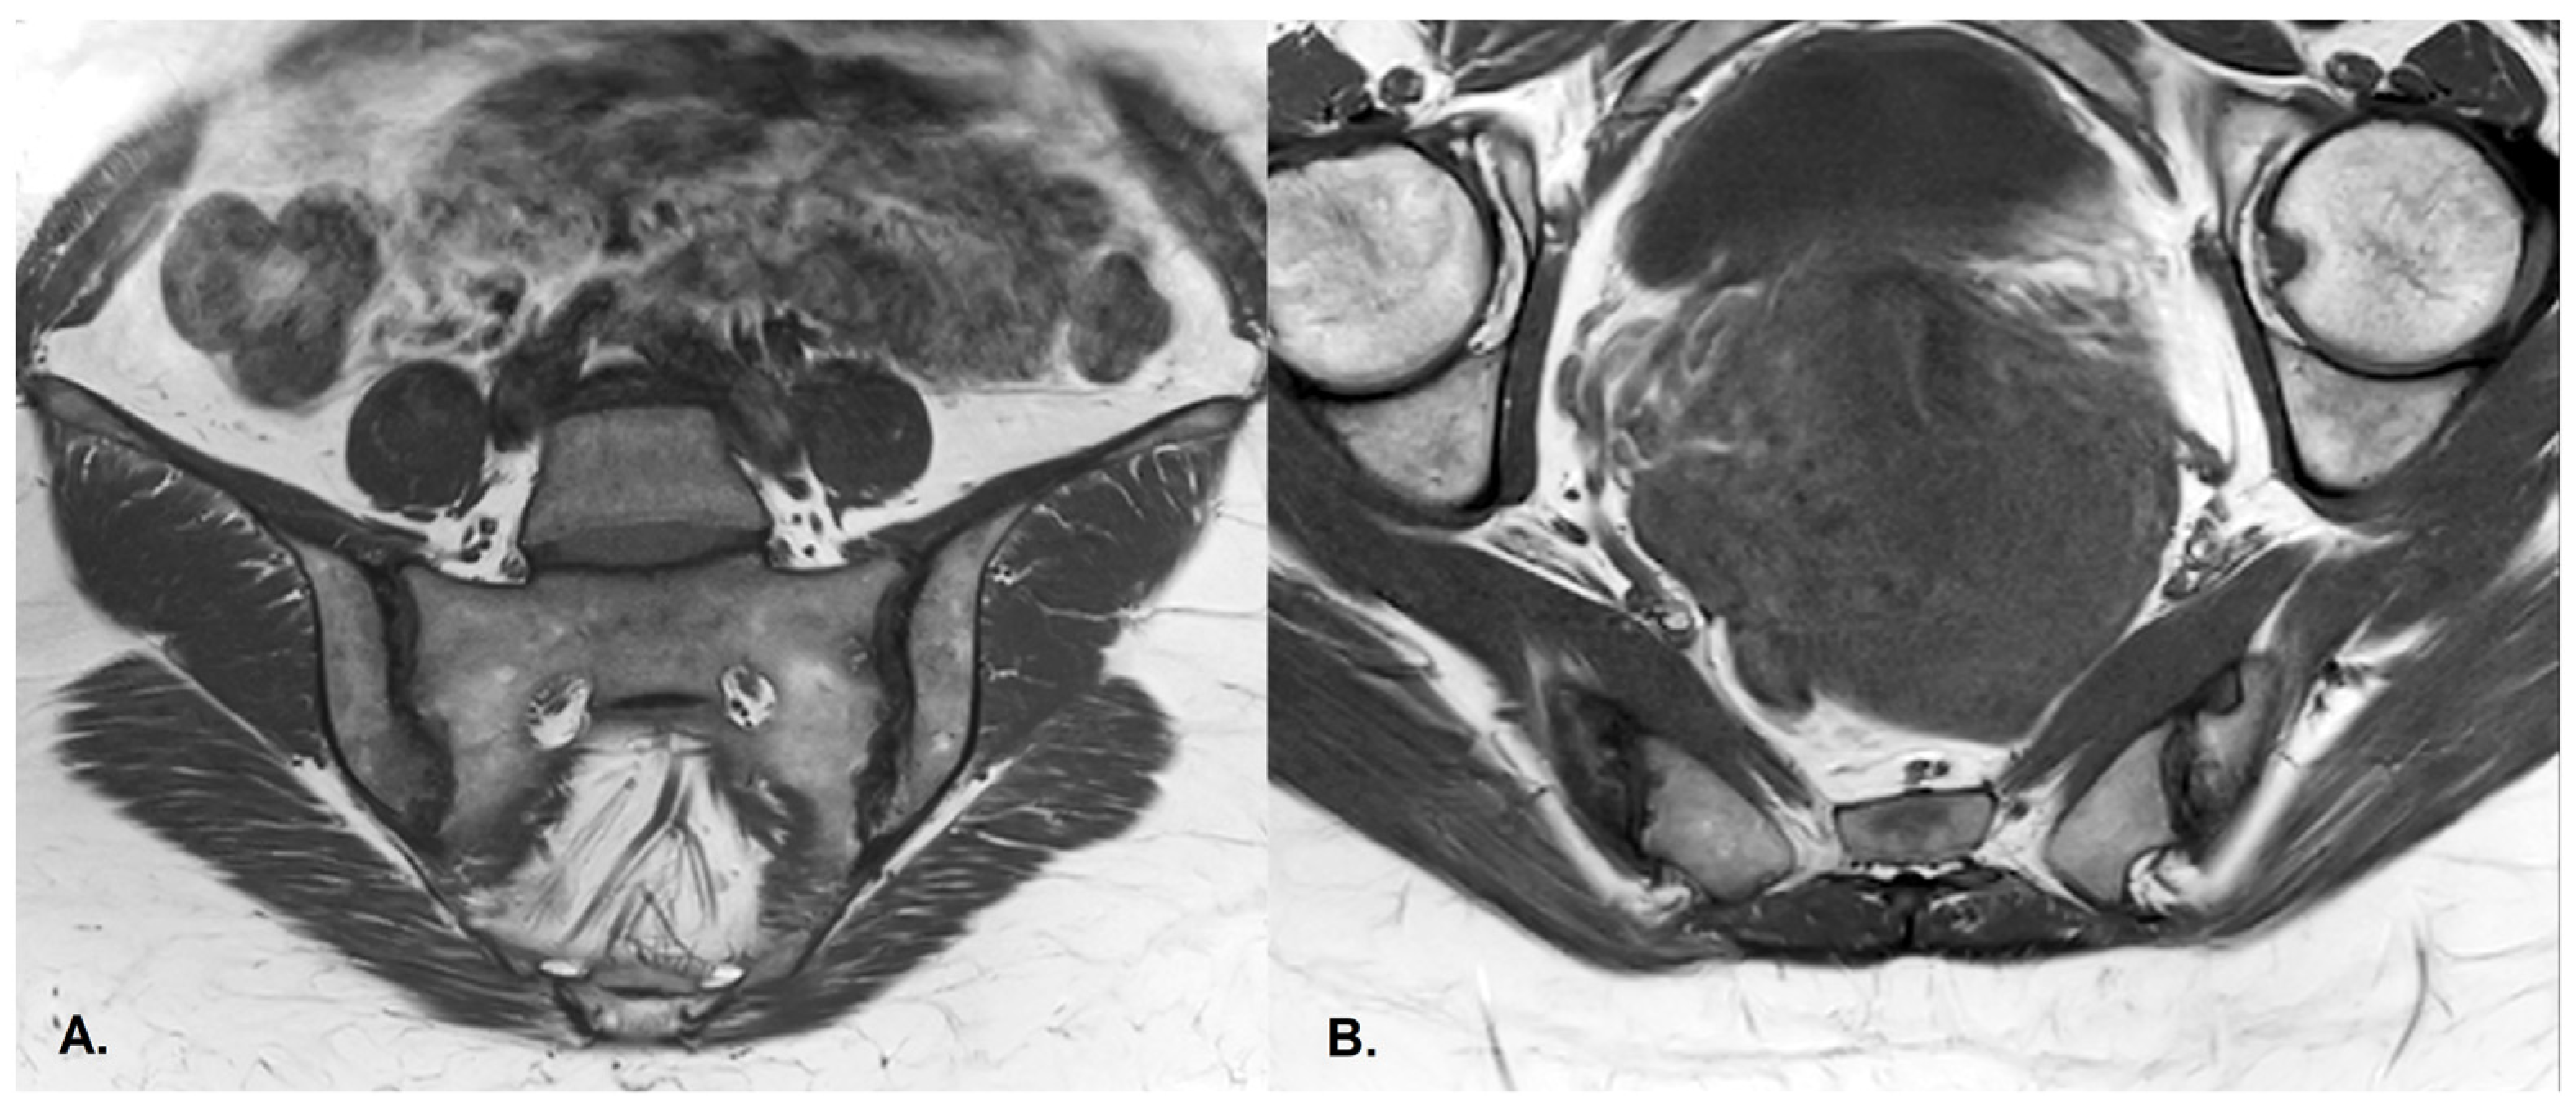

- BME is evident in low signal T1w, hyper signal T2w, STIR images and +C T1w Fat-Sat, similar to blood vessels and spinal fluid; the signal intensity is directly proportional to the inflammation activity. It is usually located periarticular to or on the subchondral bone surfaces and it is an indicator of disease activity (Figure 4) [65].

- Sclerosis—better visualized on an X-ray or CT scan; a subchondral or periarticular area with a low signal compared to normal bone marrow on T1, T1FS (SPIR), and STIR sequences (Figure 5).Slight: <25% of the subcortical bone area.Moderate: 25% to <50% of the subcortical bone area.Severe: >50% of the subcortical bone area [29].